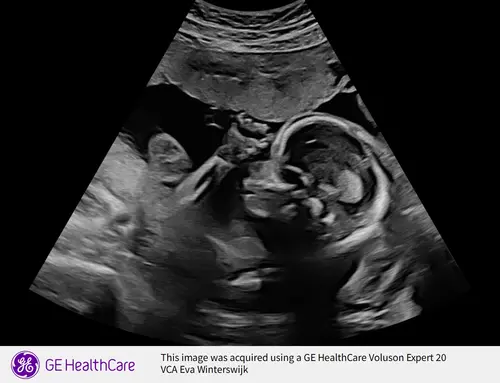

Hier ook 4 mei de uitgerekende datum 鈽猴笍 Gisteren de 20 weken echo gehad. Ook heel veel mooie echo's meegekregen. Ze had het nieuwste apparaat, echt bizar invergelijking met onze eerste dochter 5,5 jaar geleden. Dit word ons 2e dochter